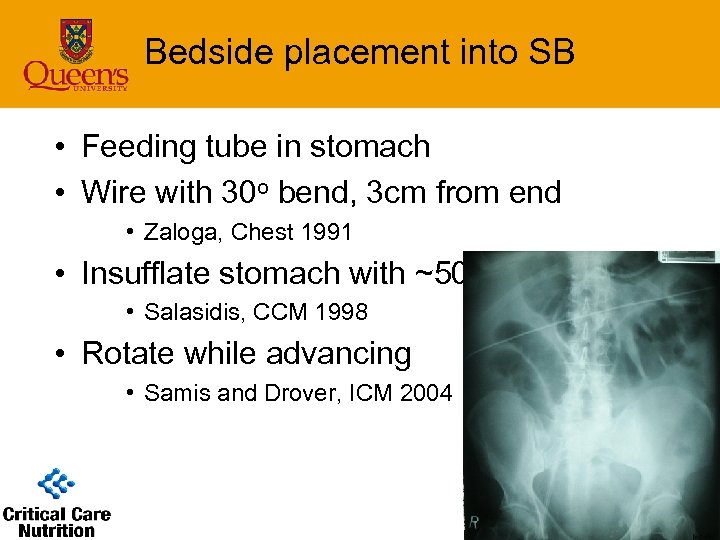

Bedside placement into SB • Feeding tube in stomach • Wire with 30 o bend, 3 cm from end • Zaloga, Chest 1991 • Insufflate stomach with ~500 ml • Salasidis, CCM 1998 • Rotate while advancing • Samis and Drover, ICM 2004

Bedside placement into SB • Feeding tube in stomach • Wire with 30 o bend, 3 cm from end • Zaloga, Chest 1991 • Insufflate stomach with ~500 ml • Salasidis, CCM 1998 • Rotate while advancing • Samis and Drover, ICM 2004